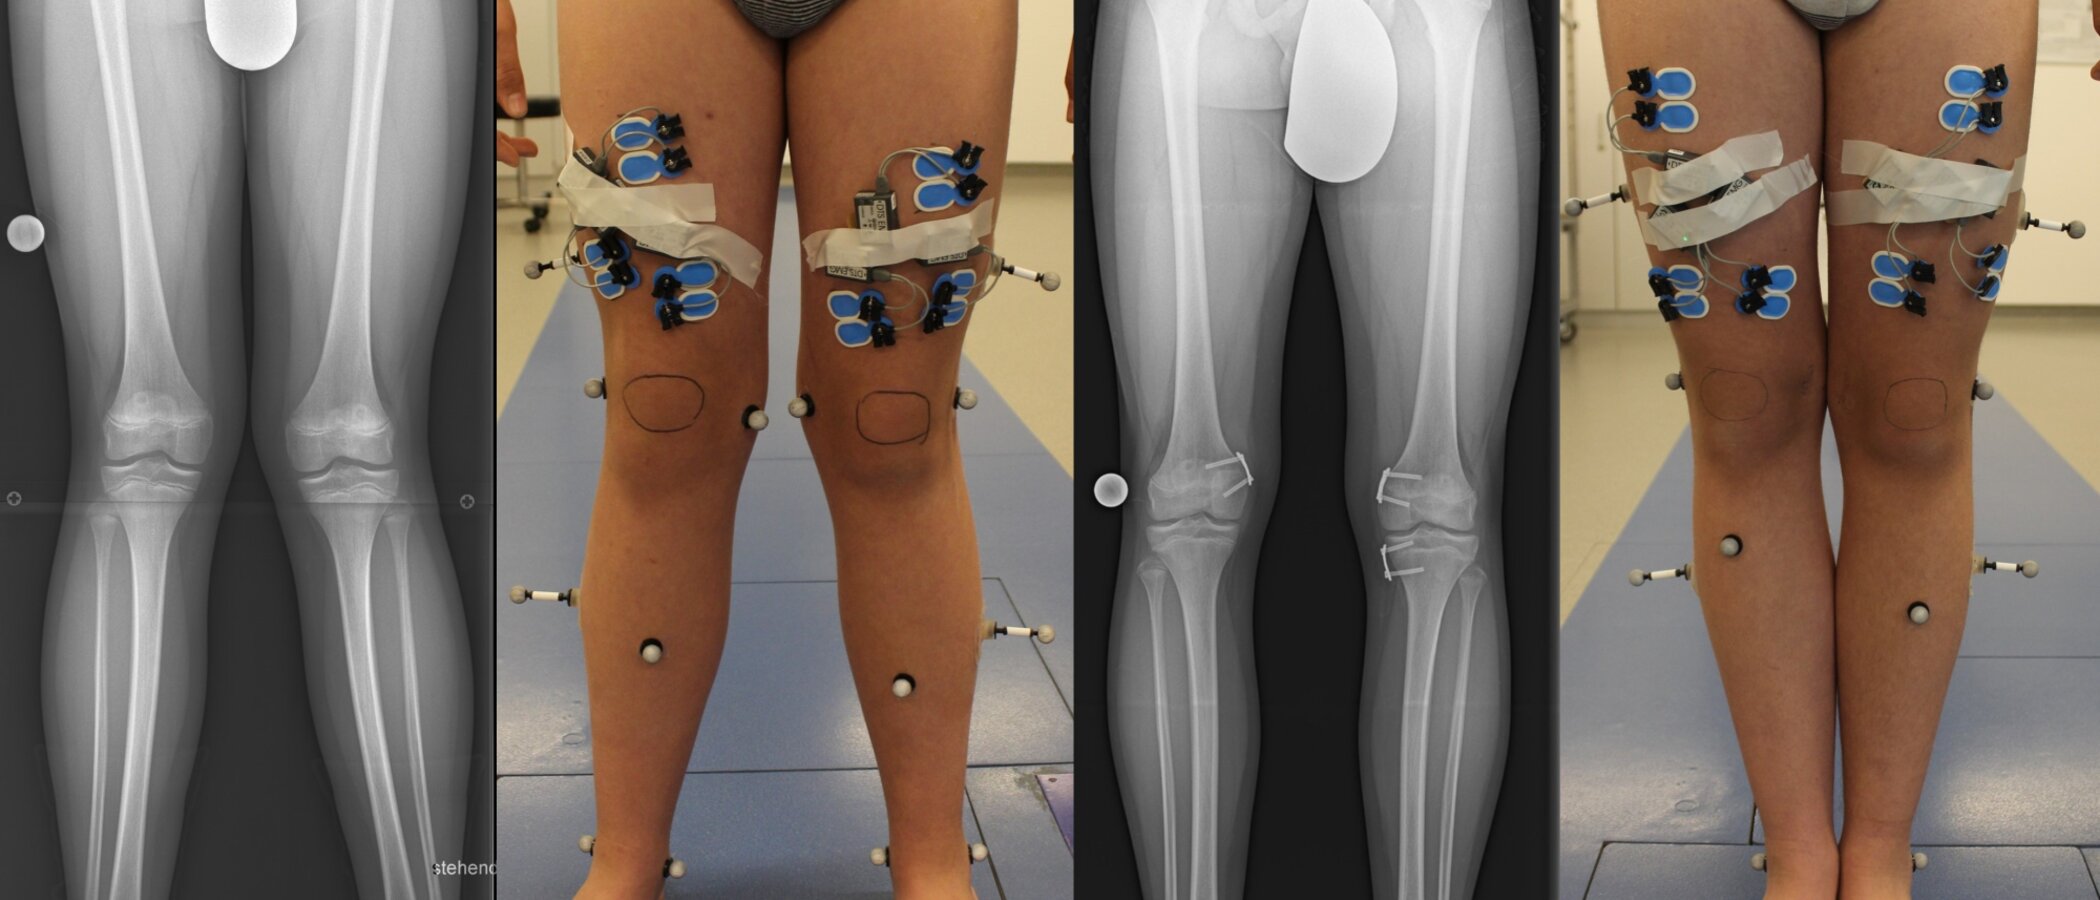

Die Wachstumslenkung bei Kindern bietet eine effektive Therapieoption, indem kleine Platten wie Eight-Plates und Schrauben an den Wachstumsfugen des Kniegelenks verwendet werden, um die Deformität frühzeitig zu korrigieren und das Restwachstum zu nutzen.

Unsere Studie zielt darauf ab, die Behandlung von Beinachsenfehlstellungen zu optimieren, indem wir präoperative Ganganalysen verwenden, um Vorhersagen über den Behandlungsverlauf zu treffen und mögliche Rebound-Effekte nach der Entfernung der Platten und Schrauben vorherzusagen.

Vor und nach der Behandlung führen wir dreidimensionale Ganganalysen durch, um Verbesserungen der Kniegelenkbelastung beim Gehen zu bewerten.